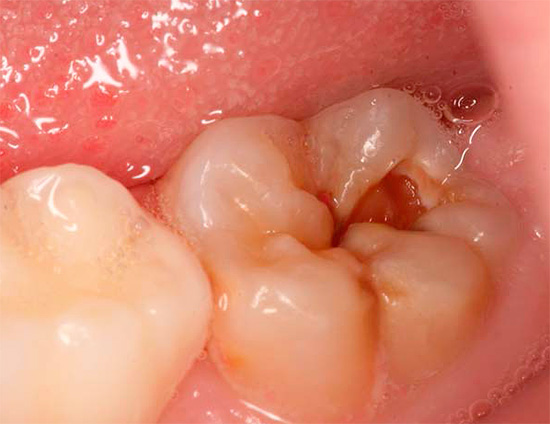

Più spesso trovato in odontoiatria pulite fibrosa cronica (in quasi il 70% dei casi), meno spesso - cancrenoso. Non si verifica quasi mai negli adulti, polmonite ipertrofica, diagnosticata solo occasionalmente all'appuntamento con un dentista pediatrico.

I sintomi della pulpite fibrosa cronica (a volte chiamata semplice cronica) sono dolore da tutti i tipi di irritanti: freddo, caldo, dolce, dall'aria fredda, ecc., Che non scompaiono a lungo dopo aver eliminato il fattore irritante. Inoltre, questa patologia specifica è caratterizzata da un sintomo così specifico come l'insorgenza di dolore prolungato durante il passaggio dal freddo a una stanza calda.

A volte la pulpite fibrosa cronica è asintomatica. Ciò è dovuto alla speciale localizzazione della cavità cariata (ad esempio, sotto la gomma), quando gli stimoli non possono influenzarla, o al messaggio passante della cavità e della camera pulpare - in tali casi non c'è gonfiore e scoppio della polpa e non ci sono dolori, rispettivamente.

L'ispezione visiva del dente con una sonda appuntita e uno specchio fornisce circa il 50% delle informazioni necessarie. In termini di aspetto della cavità, indolenzimento del suo fondo, comunicazione con la camera pulpare (il luogo in cui si trova il "nervo"), si può già ipotizzare la pulite cronica.

Se c'è un messaggio con una cavità cariata e compaiono dolore e sanguinamento quando si sondano con una sonda acuta, allora con un alto grado di probabilità è cronico pulite fibrosa. Con un cambiamento nel colore dei denti, l'aspetto di un'ombra grigia, con una grande quantità di tessuto cariato ammorbidito nella cavità del dente, quando il "nervo" viene parzialmente distrutto e il dolore si verifica solo quando si sondano i canali, allora è molto probabilmente una polpite cranica cronica. La comparsa di tessuto troppo cresciuto all'interno della cavità in combinazione con l'indolenzimento quando lo sondano il più delle volte indica una polpite ipertrofica cronica.